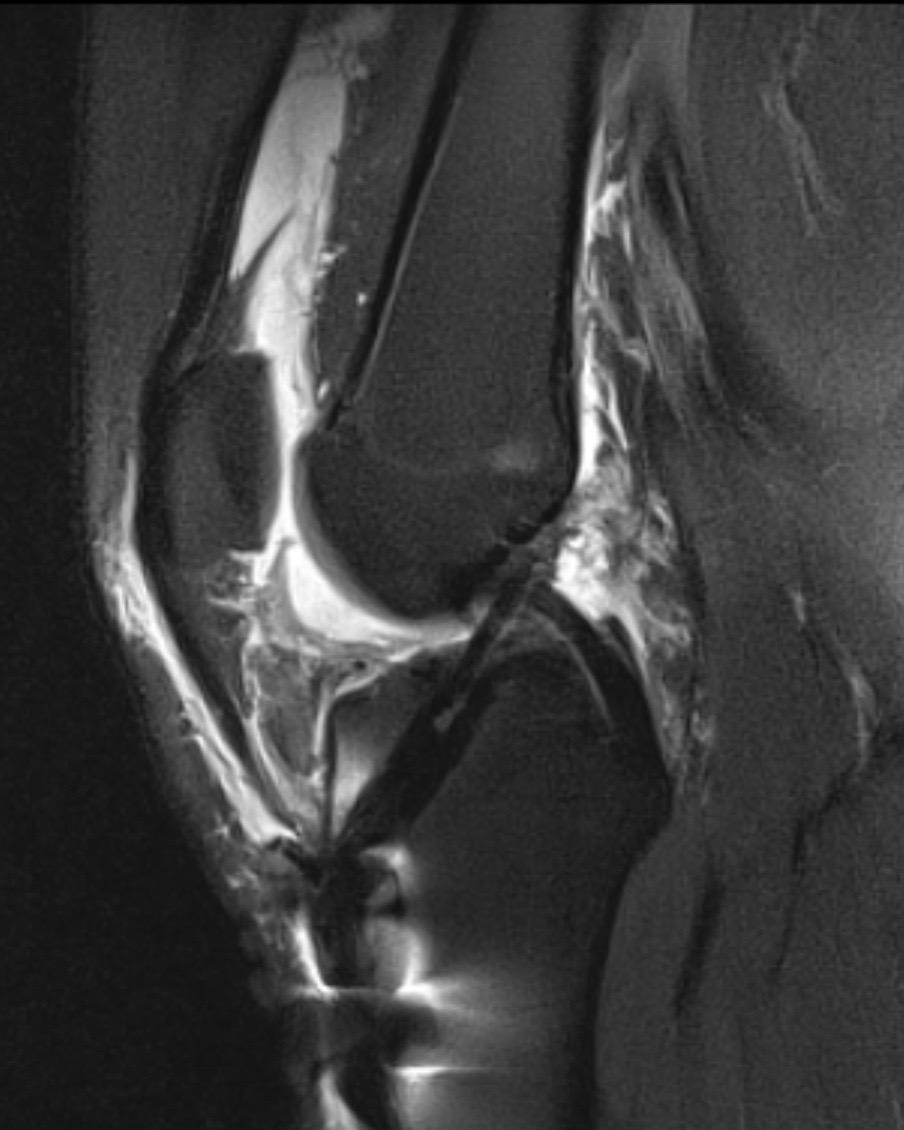

前交叉韧带重建。前叉重建+半月板修复,祝他早日康复!